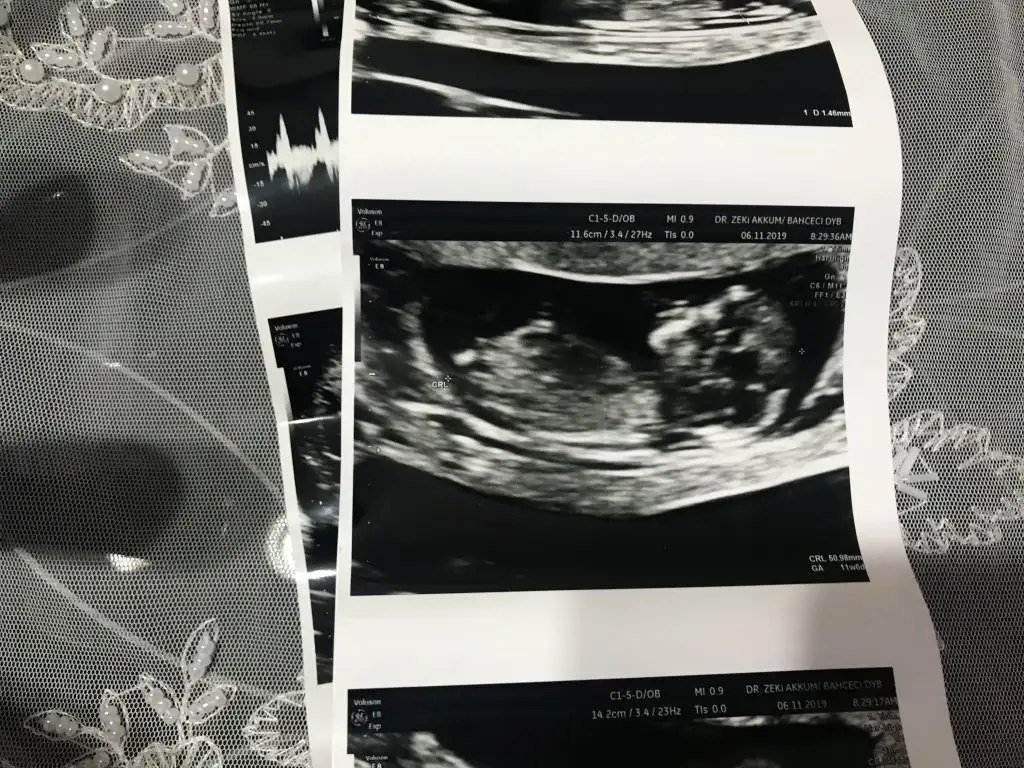

dr soylemeden siz gorun genital nub teorisi ( bebegin cinsiyeti)

Kızlar yorum istiyorum doktor daha küçük dedi 12 haftada ☺️☺️